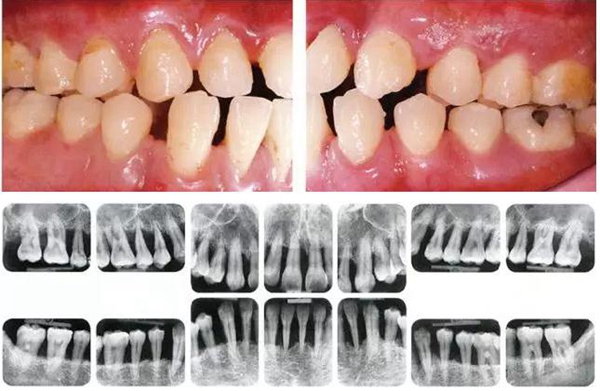

●參考病例② 25歲女性

25歲女性。菌斑控制狀態(tài)不好。齦溝除磨牙處外全在3mm以下,X光照片上左上、右下、左下的第一磨牙上有垂直性骨吸收。這個(gè)病例是參考病例①10年前的狀態(tài),是典型的侵襲性牙周炎局部型。

牙周病的發(fā)展因部位不同而發(fā)展程度不同的。10點(diǎn)后的狀態(tài)參考病例①和參考病例②的磨牙處的狀態(tài)相比較,思考下沒(méi)接受治療病情發(fā)展的特別性吧。

參考病例① 35歲女性

在左下第一磨牙在25歲時(shí)近中處可以看到垂直性的骨吸收,但35歲時(shí)吸收停止,原本沒(méi)有見(jiàn)到的遠(yuǎn)中處骨吸收的,現(xiàn)在卻吸收得很嚴(yán)重。

在右下處,原本有大量骨吸收的第一磨牙處的吸收卻變緩慢,原本沒(méi)有吸收的第二前磨牙卻出現(xiàn)了吸收。出現(xiàn)吸收的左上第一磨牙的遠(yuǎn)中處,吸收得越來(lái)越多了。

把10年間的變化做成表格。牙周病的發(fā)展根據(jù)各個(gè)人會(huì)不同,即使通一個(gè)人,不同牙齒,不同牙面發(fā)展的狀態(tài)也不同。